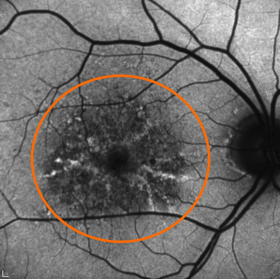

Dazu drei Beispiele anhand einer Autofluoreszenz-Laser-Aufnahme. Alle drei Patienten haben eine Sehschärfe (Visus) von 0,5 (fälschlicherweise oft im Jargon als "50%" bezeichnet). Das bedeutet, daß alle drei 2 Punkte erst als 2 Punkte sehen, wenn diese 2 Winkelminuten voneinander entfernt sind (oder erst wenn sie halb so weit von einem Objekt sind wie ein Augengesunder mit einem Visus von 1,0).

Trockene Makula-Degeneration.

Selbst mit ideal klarer Augenlinse und optimaler Brille lässt sich keine bessere Sehfunktion erreichen.

Das Licht fällt scharf auf die orange umrandete Zone der Makula, in der keine Sehzellen mehr sind.